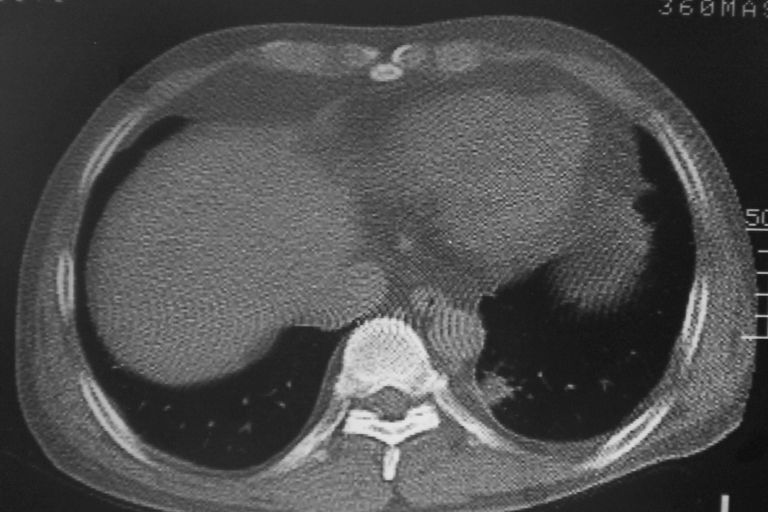

标题: CT10574:男 50岁胸部CT请会诊!

患者 男 50岁 无痛性咯血3天,无其他不适.

1 左肺下叶基底段见两结节软组织密度灶抗炎后复查

2心包积液

1 左肺下叶后基底段见结节软组织密度灶,建议抗炎后复查,排除肿瘤

1、左肺下叶两个结节影,建议抗炎治疗后复查.

2、心包积液

考虑右下肺周围型肺癌,心包积液不确切,像是脂肪

左下肺结节状软组织密度影,一个边缘有卫星病灶,邻近胸膜增厚.另一个有毛刺.心影周围水样密度影环绕.考虑:

1.肺癌可能.肺tb待排.

2.左侧胸膜增厚.心包积液.